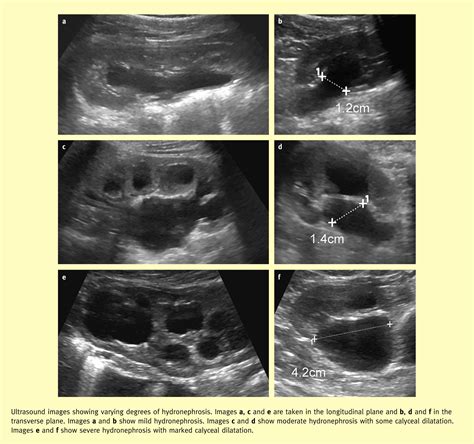

Pelviectasis can be classified into two main types based on the severity of the dilation:

• Mild Pelviectasis: This type involves minimal dilation of the renal pelvis and is often considered a normal variant. It typically does not require treatment and is monitored regularly.

• Severe Pelviectasis: This type involves significant dilation of the renal pelvis and may indicate an underlying obstruction or other serious condition. It often requires medical intervention.

• Ultrasound: An ultrasound of the kidneys and urinary tract is the primary diagnostic tool for detecting pelviectasis. It provides detailed images of the renal pelvis and can help determine the extent of dilation.